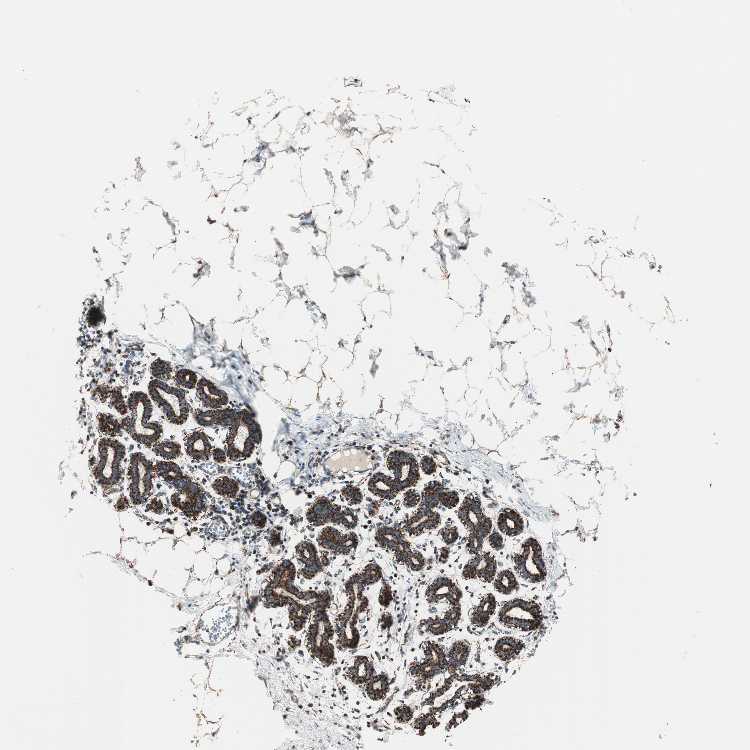

BREAST - Antibody stainingi

Antibody staining in the annotated cell types in the current human tissue is reported as not detected, low, medium, or high, based on conventional immunohistochemistry profiling in selected tissues. This score is based on the combination of the staining intensity and fraction of stained cells.

Each image is clickable and will lead to virtual microscopy that enables deeper exploration of all samples and also displays staining intensity scores, fraction scores and subcellular localization as well as patient and tissue information for each sample.

Antibody HPA003037

Adipocytes Medium

Glandular cells High

Myoepithelial cells High